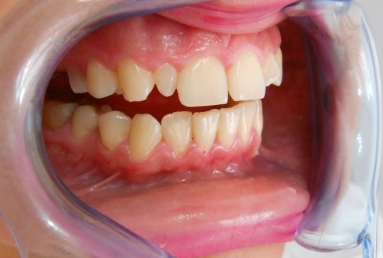

Very small lateral incisors covered with full ceramic crowns and ceramic veneers on central incisors. The prosthetic space was correctly split between the four incisors, in order to reduce the disproportion between the large centrals and the very small laterals. The preparation of the teeth was minimally invasive, all four incisors remained vital.